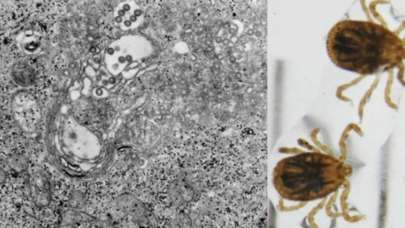

Çin yeni bir salgın konusunda uyardı!

5 yıl önce